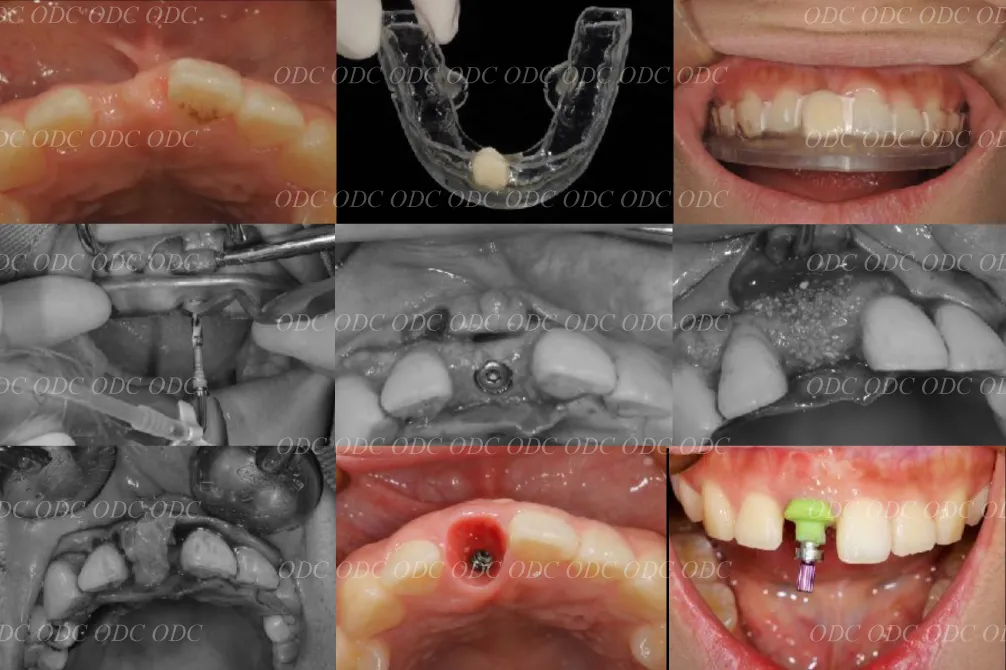

前歯部少数歯欠損症例

2014年、前歯1本欠損でインプラント治療を希望されて来院されました。

サージカルガイドを作成しインプラント埋入を行っていきました。

骨造成 結合組織移植等を行いながら最終印象を行っていきました。

最終補綴装着後の口腔内写真です。自然な仕上がりにご満足頂いております。